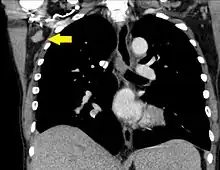

| A CT scan of axillary lymphadenopathy in a 57-year-old man with multiple myeloma. | |

Lymphadenopathy of the axillary lymph nodes can be defined as solid nodes measuring more than 15 mm without fatty hilum.[36] Axillary lymph nodes may be normal up to 30 mm if consisting largely of fat.[36]